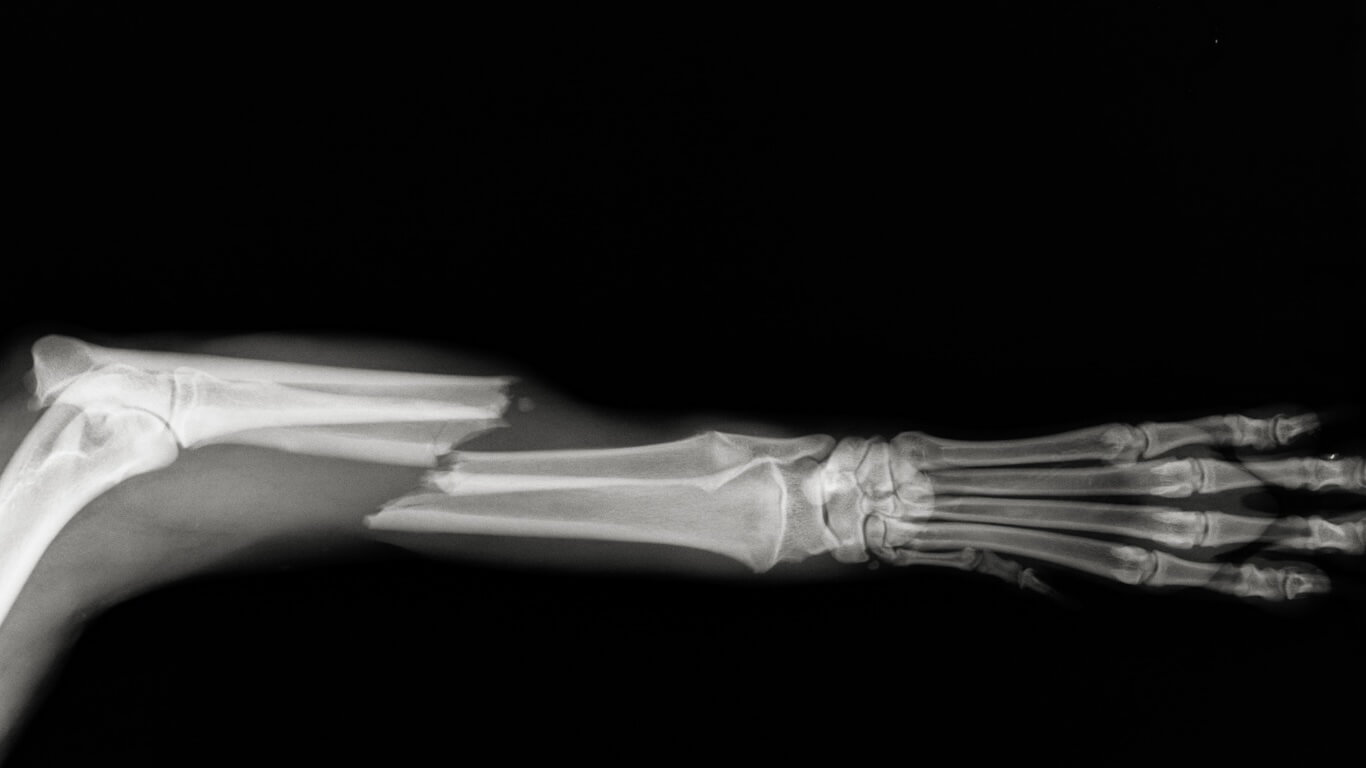

Radiographs, or x-rays, use electromagnetic radiation directed towards the body to highlight objects within. They can detect abnormalities including skeletal fractures, soft tissue damage, foreign bodies, and dental disease.

Orthopedic radiographs and contrast studies require the patient remain completely still to work correctly, necessitating sedation in most cases. Some specialized procedures may require anesthesia. The duration of sedation or anesthesia is usually short and patient recovery is swift.